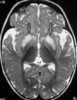

Infantile familial encephalopathy with cerebral calcification and leukodystrophy

Intracranial calcification